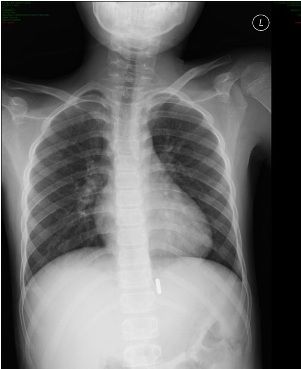

In the digestive tract, the magnets can aggregate and cause sequelae as grave as intestinal torsion and blood poisoning. The images at left show a radiograph demonstrating multiple magnets connected in the stomach (left), which on an endoscopic retroflex view of the stomach cardia and gastroesophageal junction (below) were pinching mucosa and causing pressure ulceration. Forceps are visible trying to dislodge the magnets.

An abdominal radiograph should be obtained in any case of suspected ingestion. It is also recommended to obtain 2 views to clarify if there is more than 1 magnet involved.